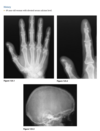

Foot pain

A lateral radiograph of the left foot demonstrates a prominent talar beak

­ (arrow) and bony sclerosis overlying the middle

facet (arrowheads). Coronal CT through the middle

facet shows talocalcaneal fusion, with bony bridging between the talus and the sustentaculum tali of the

calcaneus

Diagnosis: Tarsal coalition

abnormal fusion

of one or more of the tarsal bones, may be fibrous,

cartilaginous, or osseous and may be posttraumatic, or congenital.

Most

common tarsal coalitions are calcaneonavicular and

talocalcaneal.

Radiographically, calcaneonavicular coalition may

be suspected because of elongation of the anterior

facet of the calcaneus on radiographs (i.e., anteater

sign. CT can also be used to confirm coalition and shows

­ sclerosis at the articulation

Congenital coalition usually evolves from fibrous to osseous

coalition and may not be apparent on the initial

evaluation

Talocalcaneal coalition can result in dorsal beaking

of the talar head (Fig. 2.3.6, arrowhead), the so-called

C-sign (arrows)